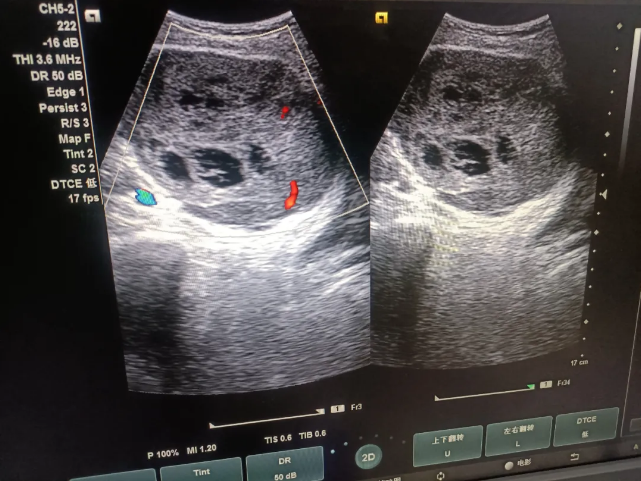

果然,检查结果显示:腹腔内膀胱上方探及一低回声区,大小约93mmx92mmx76mm,边界清晰,形态尚规则,其内可见蜂窝样无回声,周围血管受压,CDFI:其内可见点条状血流信号。结论:腹腔内实性肿块伴少量液化,建议穿刺活检。